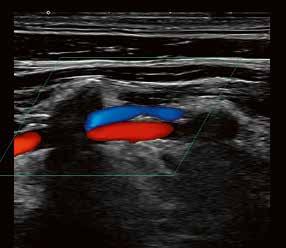

60 Ein Plädoyer für hochwertige Ultraschallausrüstung in der neurologischen Praxis

ULTRASCHALL